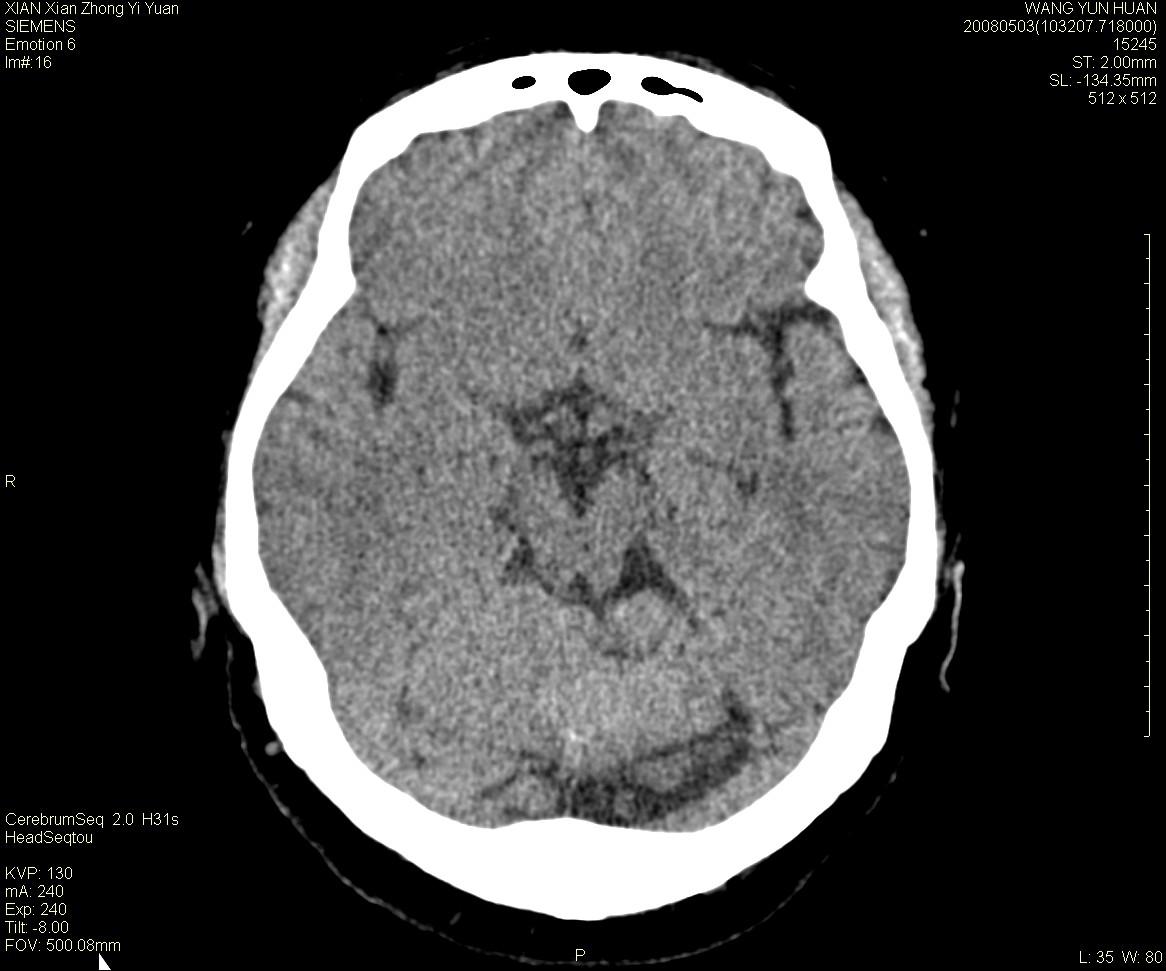

标题: CT13219:(补充强化)请会诊,患者女,60岁,头晕,大家看 [打印本页]

标题: CT13219:(补充强化)请会诊,患者女,60岁,头晕,大家看

病灶显示轻度强化,ct增加4hu左右,大家看是什么肿瘤.

强化后动脉期及延迟2分钟,五分钟图像

小脑蚓部囊型肿块,内有实性结节及钙化点。增强后囊壁及结节轻度强化。

考虑蚓部星形细胞瘤(ⅱ级可能性大)。

小脑蚓部肿块,周围无明显占位效应及水肿带,增强轻度强化,考虑低分级星形细胞瘤。

小脑吲部胶质瘤(少枝胶质细胞瘤或形星细胞瘤)